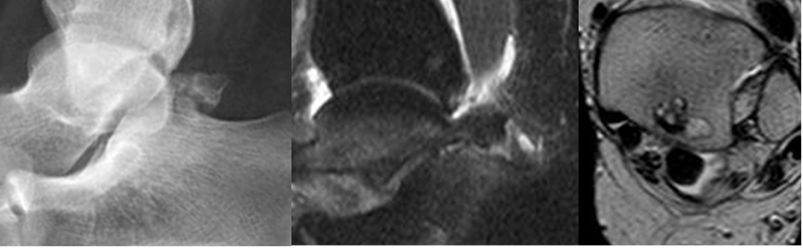

Fig 101 A. Pinzamiento posterior.

TAC reconstrucción sagital. Presencia de os trígonum.

Fig 101 B. Pinzamiento posterior por os trígonum.

A: Rx lateral y B: RM sagital en STIR. Os trígono hipertrófico, que ocasiona pinzamiento y signos de sinovitis.

C: Engrosamiento del flexor largo del hallux, el cual está rodeado por líquido, por tendinitis crónica y tenosinovitis.